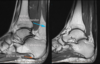

What is imaging used for in Achilles Tendinopathy?

Look for tear or calcification with Ultrasound or MRI

Where on the tendon does Achilles Tendinopathy occur?

Mid-tendon > Calcaneal insertion